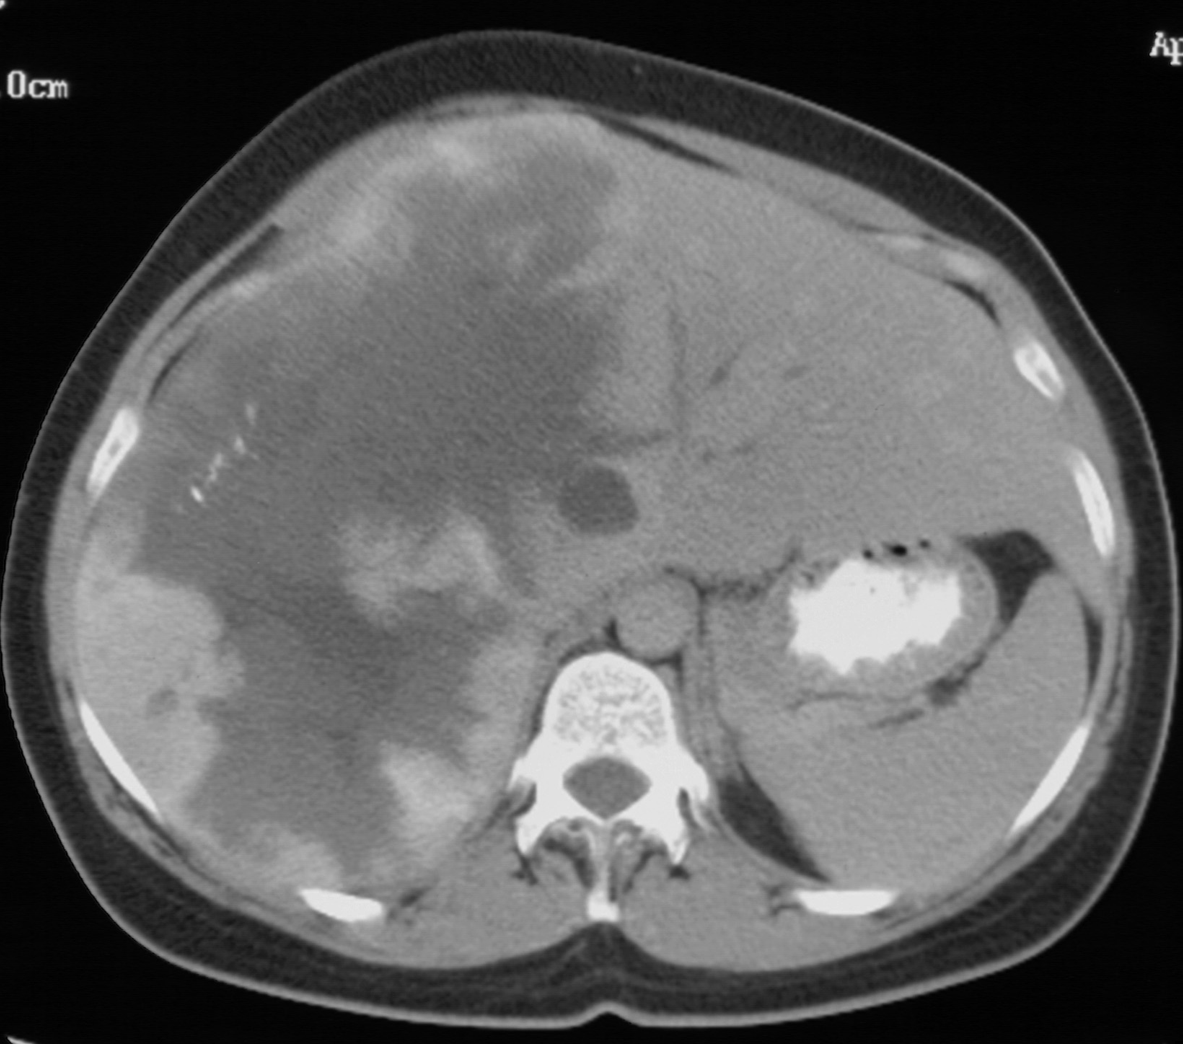

Benign Cavernous Hemangioma. Asymptomatic for 6 years. The patient develops early satiety and abdominal distention and fullness. R hepatectomy was straightforward. Early control of R portal vein and R hepatic artery necessary and made procedure safe and nearly blood less.